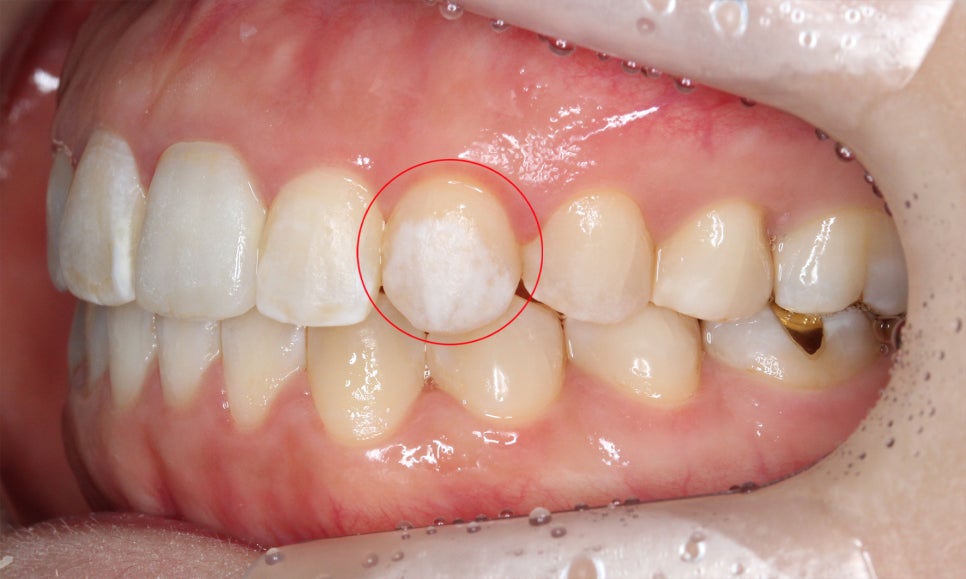

양악교정 전 치아의 교합평면 모습을 보면

송곳니교정을 하지 않아 견치의 높이가

상당히 올라가 있는 모습입니다.

덧니의 경우 영구치가 맹출되는

시기로 인해 송곳니에서 주로

발생하게 되는데요, 이러한 덧니는

종종 회전되거나 틀어진 치아와

혼동하기 쉽습니다.

이러한 치아들과 덧니를 구별하는

가장 쉬운 방법은 위처럼 치아가

맹출된 높이를 확인하는 것인데요,

위의 Case처럼 송곳니가 주변 치아들보다

더 위쪽으로 뻐드러지게 맹출되어 있는 것을

high canine라고 합니다.

상대적으로 다른 치아들보다 뿌리가 깊고

2D교정 시 기둥의 역할을 하기 때문에

위와 같은 송곳니의 덧니는 교정이 까다롭고

치료시 주의를 기울여야 합니다.

송곳니교정 전 상악의 교합면을 보면

사진에서 좌측 송곳니가 입술 방향으로

뻐드러지게 나가 있는 모습을 확인할 수 있습니다.